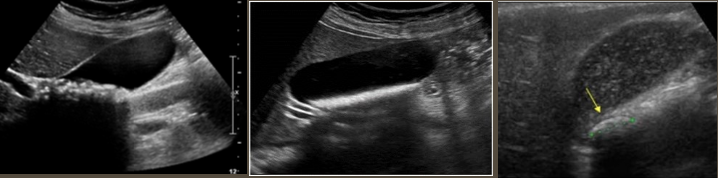

Simple Renal Cyst → common lesion of kidney, fluid-filled sac (benign, Bozniak 1)

2D US: anechoic, well-defined smooth, thin wall, round or ovoid, posterior enhancement

color doppler: avascular

Complex Renal Cyst → any cyst that is not a simple cyst

2D US: well-defined cystic structure, internal echoes or anechoic, septations, focal hypoechoic inner mural extension, can be hemorrhagic

color doppler: if solid can have vascularity